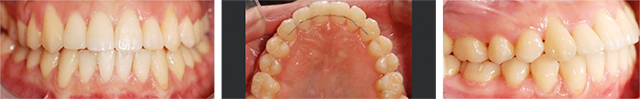

공간부족으로 인하여 치아가 제대로 나오는 못한 2급 부정교합 환자입니다. 고운미소에서 악궁을 넓혀주는 급속구개확장술 (RPE)를 적용하여 비발치 교정을 진행하였습니다.

급속구개확장술 (RPE) 장치로 빠르게 상악이 확장되었습니다. 넓어진 공간으로 치아가 이동이 되어 발치를 하지 않고 가지런하게 치아교정이 되었습니다.